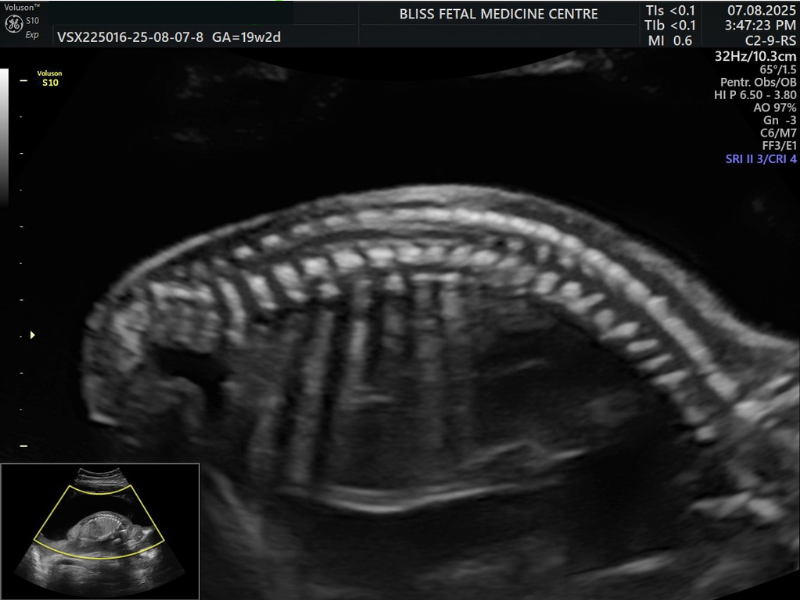

4. Detailed Anomaly Scan

The Detailed Anomaly Scan is similar to a standard ultrasound scan but provides detailed information. Here, fetal anatomy is assessed to ensure that the baby develops normally, especially by measuring the parts of the body to see how well it is growing.

When Is It Performed?

- It is a second-trimester scan performed between 18 and 23 weeks.

- It helps determine the presence of Spina Bifida (Open Spinal Cord).

- It is also done when special attention is needed for the baby’s brain, face and other vital organs.